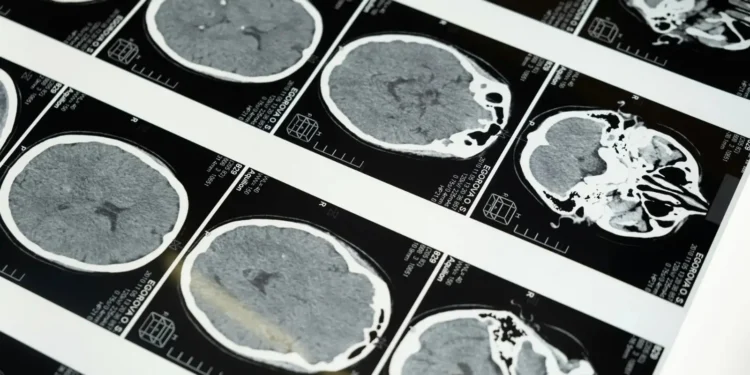

O exame indicou uma hemorragia intracraniana devido à queda que o presidente sofreu em outubro. Lula foi então transferido para a capital paulista, onde foi submetido a uma craniotomia para drenagem de hematoma. A cirurgia transcorreu bem e o chefe do Executivo é monitorado em leito de UTI.

“É feito um pequeno furo no crânio. Não há acesso ao cérebro propriamente. Você faz esse furo para acessar o espaço subdural, anterior ao cérebro, onde é colocada uma cânula – similar a um canudo – que aspira esse conteúdo [hematoma]. Depois, você fecha esse buraco, e o paciente tem vida absolutamente normal”, detalha o especialista.Play Video

Ainda segundo Brainer, o sangramento que Lula teve pode exercer efeito compressivo no cérebro.

“À medida que ele vai apertando [o cérebro], pode causar sintomas, que podem ser desde uma dor de cabeça até prostração, astenia [falta de energia], dificuldade de fala ou de movimentação.”